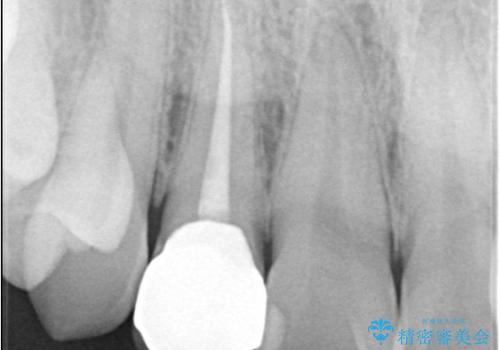

右上2番の歯に自発痛を認め、症状や歯髄診・レントゲン像から不可逆性歯髄炎と診断し、精密根管治療から歯冠補綴まで行うこととなりました。

初診時に歯髄診断を行い、不可逆性歯髄炎と診断し抜髄から補綴修復までの流れを説明し、精密根管治療、ファイバ-コア築造、オールセラミッククラウン(St)修復を行うこととしました。